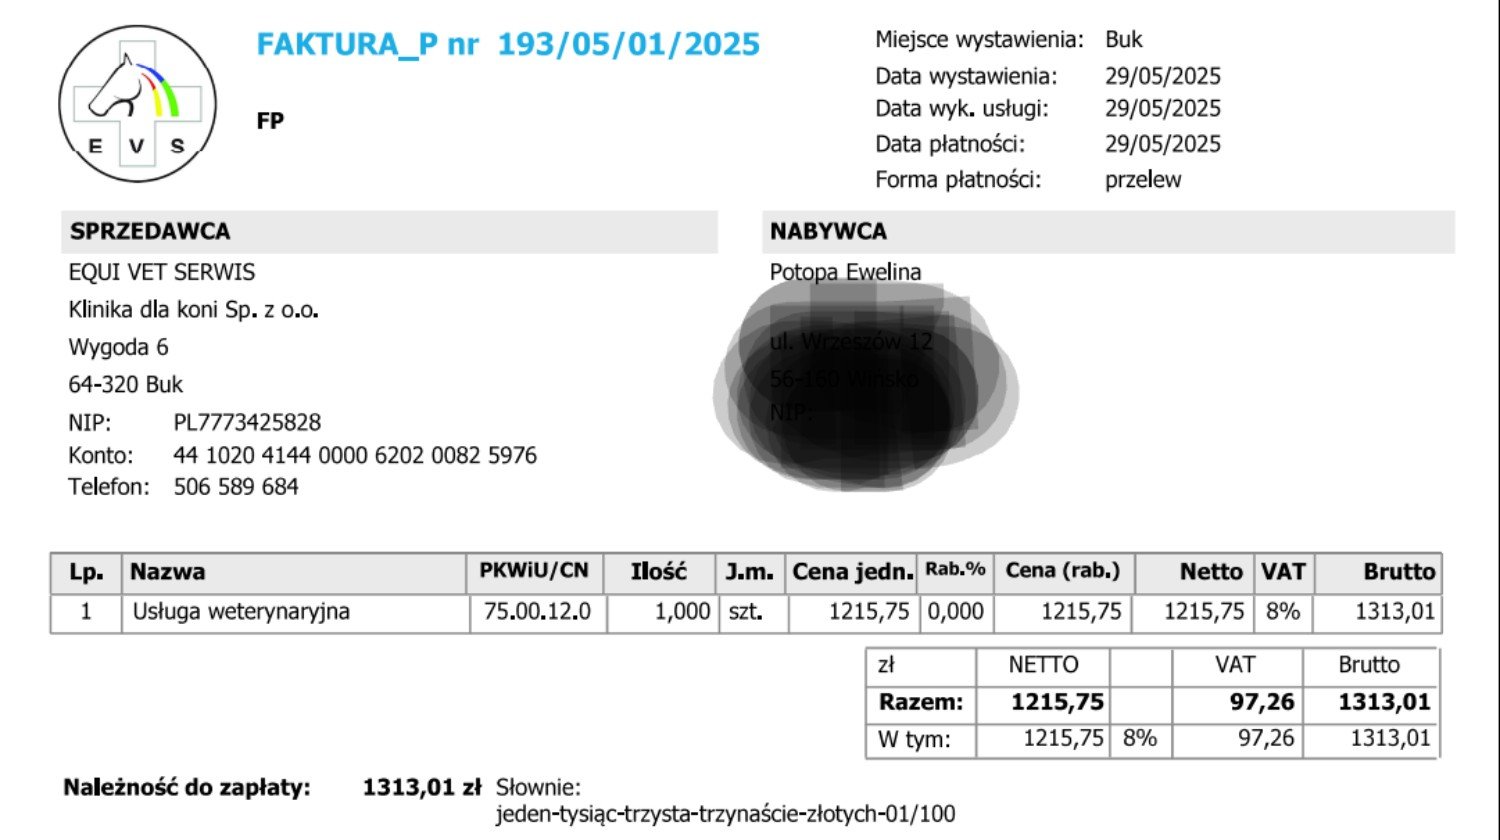

Aktualizacja 30.05

Załączam screeny faktur z kliniki. Koń przeszedł operację bez komplikacji, za około trzy miesiące będzie wiadomo coś więcej.